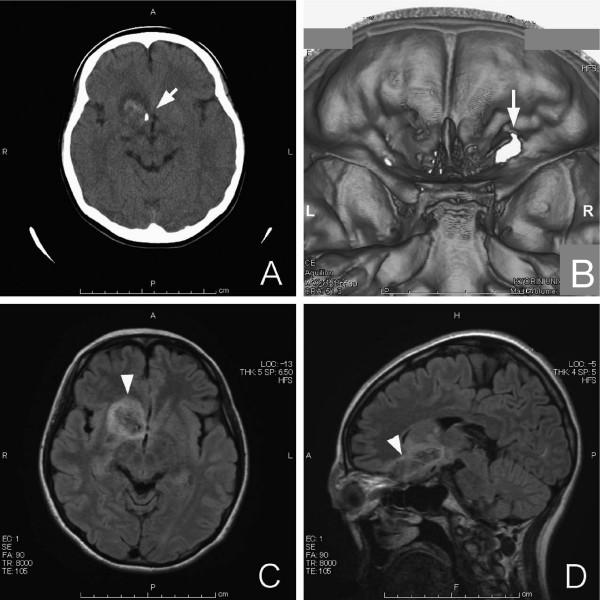

A 17-year-old Japanese woman complained of decreased vision in her right eye, with severe ocular pain and headaches, after the metal tip of an umbrella struck her upper right eyelid accidentally. Her vision in the right eye decreased to light perception with commotio retinae, intraretinal hemorrhage, and severe lid swelling. Magnetic resonance imaging (MRI) demonstrated edema of the head of the caudate nucleus and putamen, and the edema extended to the hypothalamus. The MRI findings indicated that the umbrella tip had penetrated through the eyelid and the posterior orbital wall. Vision improved to 20/50 in the right eye, with subretinal fibrosis caused by the choroidal rupture.

We recommend that MRI be performed on the orbit and brain in patients who appear to have symptoms that are inconsistent with the observed injury and when a severe orbitocranial injury is suspected.